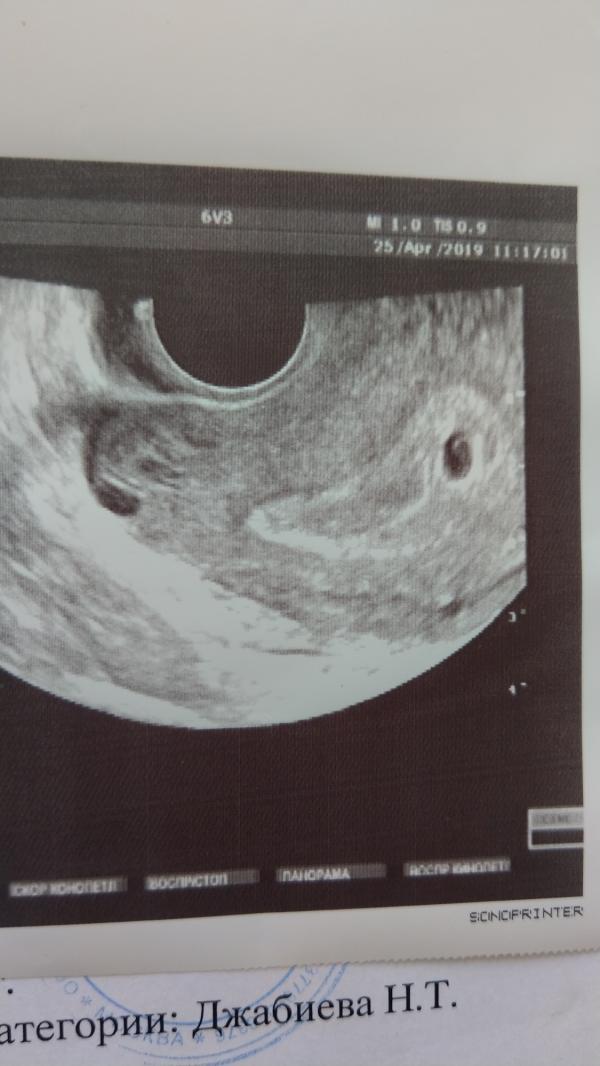

пришел хгч 2583 мЕ. (неделю назад был 572 мМЕ) прогестерон 4,49 мкг/л (назначила утрожестан 200мг 3р в день)… Выделения светло-коричневые идут… сказала — лежать. На узи, действительно, максимум 8 мм плодное яйцо (По внутреннему диаметру даже 6мм), НО! мы смогли разглядеть похожее на желточный мешочек круглишок и даже уплотнение с одной стороны… Конечно, самое главное — набраться терпения и ждать, молиться и верить…. Эта неделя решающая… через 5дней сдать контроль ХГЧ. и 2-3 мая на узи. срок 3-4 недели

Как думаете, видно на узи желточный мешочек?